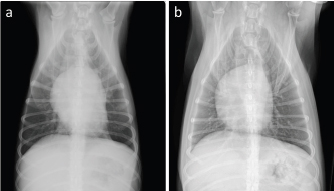

An 8-year-old, castrated, mixed-breed dog weighing 14.2 kg was referred to the Veterinary Medical Center, Obihiro University of Agriculture and Veterinary Medicine, for investigation of superficial lymph node enlargement for 1 month. Based on cytological findings and clonality analysis (Lana et al., 2006), the dog was diagnosed with multicentric high-grade B-cell lymphoma, clinical stage V (sub-stage b). The dog received l-asparaginase (5,000 IU/m2, SC) for induction, which was complicated by tumor lysis syndrome. After recovery from tumor lysis syndrome, treatment with 25-week multi-agent chemotherapy (Garrett et al., 2002), which consisted of vincristine (0.5 mg/m2, IV), cyclophosphamide (250 mg/m2, IV), doxorubicin (25 mg/m2, IV), and prednisolone (2 mg/kg, PO, q24h), was administered from April to October 2018 (Fig. 1). The patient achieved complete remission and was doing well, but the lymphoma relapsed 6 months after first-line chemotherapy. Reinduction was attempted using the same protocol from April to October 2019, which replaced third and fourth doxorubicin with mitoxantrone because of the risk of cumulative toxicity of doxorubicin. The cumulative doxorubicin dose was 125 mg/m2. Before second doxorubicin, echocardiographic examination was performed, showing normal cardiac function with an estimated left ventricular ejection fraction (LVEF) of 68.6% and left ventricle fractional shortening (LVFS) of 37.6% (Fig. 2a). In addition, diastolic and systolic left ventricular wall thicknesses were 8.6 and 14.2 mm, respectively. A mitoxantrone dose of 4 mg/m2 was administered twice. The dog achieved a second complete remission, but relapsed again 6 months after second-line chemotherapy. Subsequently, the dog received third-line chemotherapy, including epirubicin (25 mg/m2, IV) and vincristine, resulting in high cytocidal effects. One week after five cycles of epirubicin (cumulative epirubicin dose, 125 mg/m2), the dog was admitted to the hospital with a history of orthopnea, swelling of legs, and fatigue. On physical examination, muffled heart sounds were identified. Thoracic radiographs revealed generalized cardiomegaly (Fig. 3), and vertebral heart size was 11.5 (normal range, 9.7 ± 0.5 vertebrae). Electrocardiography (ECG) showed accelerated idioventricular rhythm with a wide QRS complex (Fig. 4). Echocardiography revealed severe diffuse hypokinesia with an LVEF of 46.4% and LVFS of 18.8% (Fig. 2b), and reduced diastolic and systolic left ventricular wall thickness (7.0 and 8.6 mm, respectively). Troponin I was 1.185 ng/ml (FUJIFILM VET Systems, Tokyo, reference range; 0.006–0.129 ng/ml). Based on these findings, a diagnosis of anthracycline-induced cardiomyopathy (AICM) was established. The dog was treated with benazepril (0.32 mg/kg, PO, q24h) and pimobendane (0.16 mg/kg, PO, q12h). Seven days after the treatment for cardiomyopathy, the dog was clinically stable, and echocardiography revealed improved cardiac function with LVEF of 66.2% and LVFS of 30.4%. However, after 9 days, the condition worsened, and a large number of lymphoblast cells were observed in the peripheral blood smear of the dog. Cytosine arabinoside (300 mg/m2, IV, drip infusion for 3 hours) was administered, but the dog subsequently died 22 days after the diagnosis of cardiomyopathy. Necropsy was not performed.

Fig. 3. Thoracic radiographs of the case. On comparing with that (a): before first doxorubicin administration, (b): generalized cardiomegaly was observed at 1 week after the administration of six cycles of epirubicin.